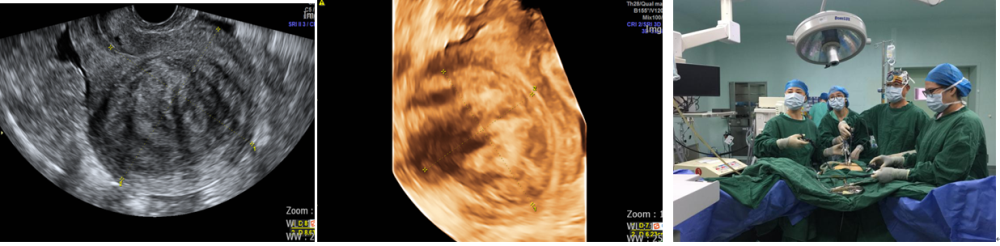

案例8:方**,女,44岁,高强度聚焦超声治疗治疗前和治疗后20天。